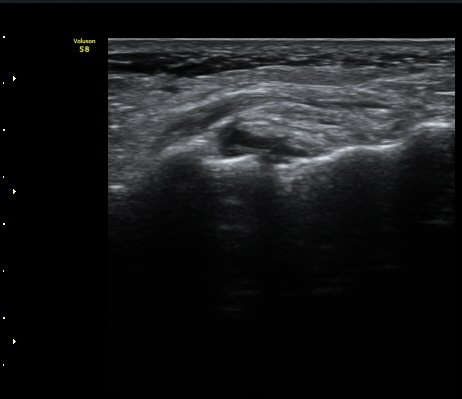

Àδë Á¾°ñºÎÂøºÎ Á¾´Ü¸é°Ë»ç¿Í Ⱦ´Ü¸é°Ë»ç¿¡¼­ Á¾°ñÀÇ °ß¿­°ñÀýÀÌ °üÂ÷µÊ(»çÁø 4, 5).